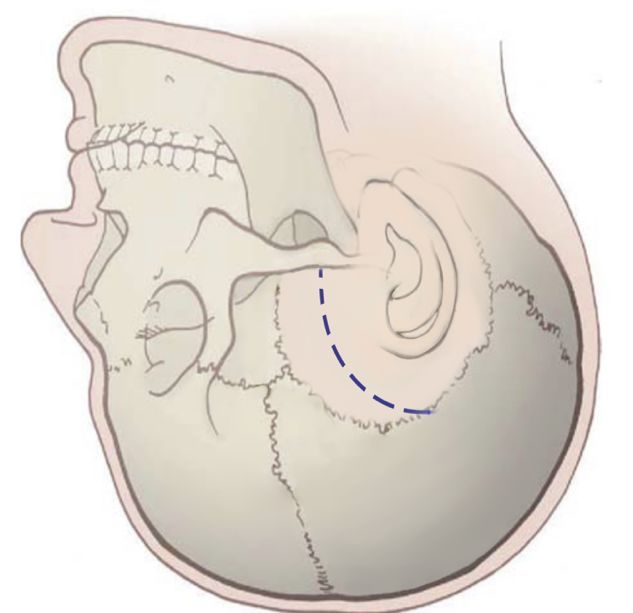

手术方式:颞下经天幕入路

2 脑干出血部位位于基底部和被盖部之间,而后影响到其他脑干分区,手术尽量在脑干安全区进入,以免加重神经功能的损伤。

在全麻下行颞下经天幕入路,脑干血肿清除术

在脑干安全区切开脑干约 5mm

本例病人,出血位于脑干基底部和被盖之间,逐渐向其他分区蔓延,选择侧方安全区入路,既不损伤脑干基底部的长传导束,又不损伤被盖部的生命中枢,术后取得了较好的效果。